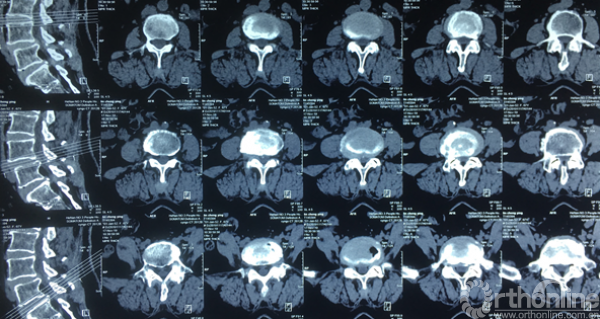

术前CT示:1.腰椎退行性变;2.L4椎体滑脱;3.腰椎管狭窄症;4.相应神经根硬膜囊受压。

术前CT